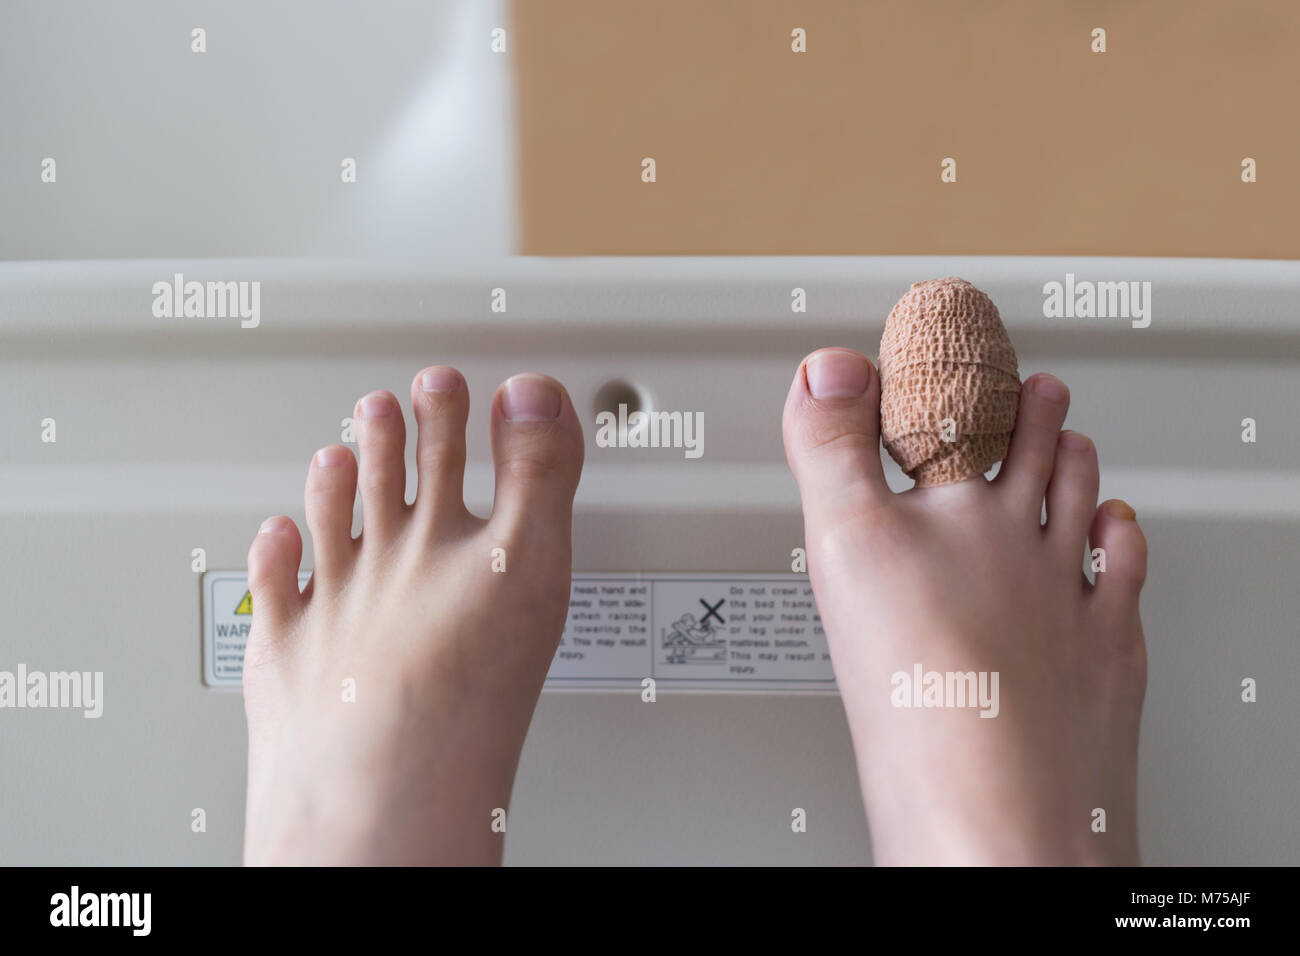

RFM75AJF–Nahaufnahme der Verband index Zehe der weiblichen Patienten schlafen im Bett des Patienten nach einem Unfall

RFM75AKY–Nahaufnahme der Verband index Zehe der weiblichen Patienten schlafen im Bett des Patienten nach einem Unfall mit Sunbeam